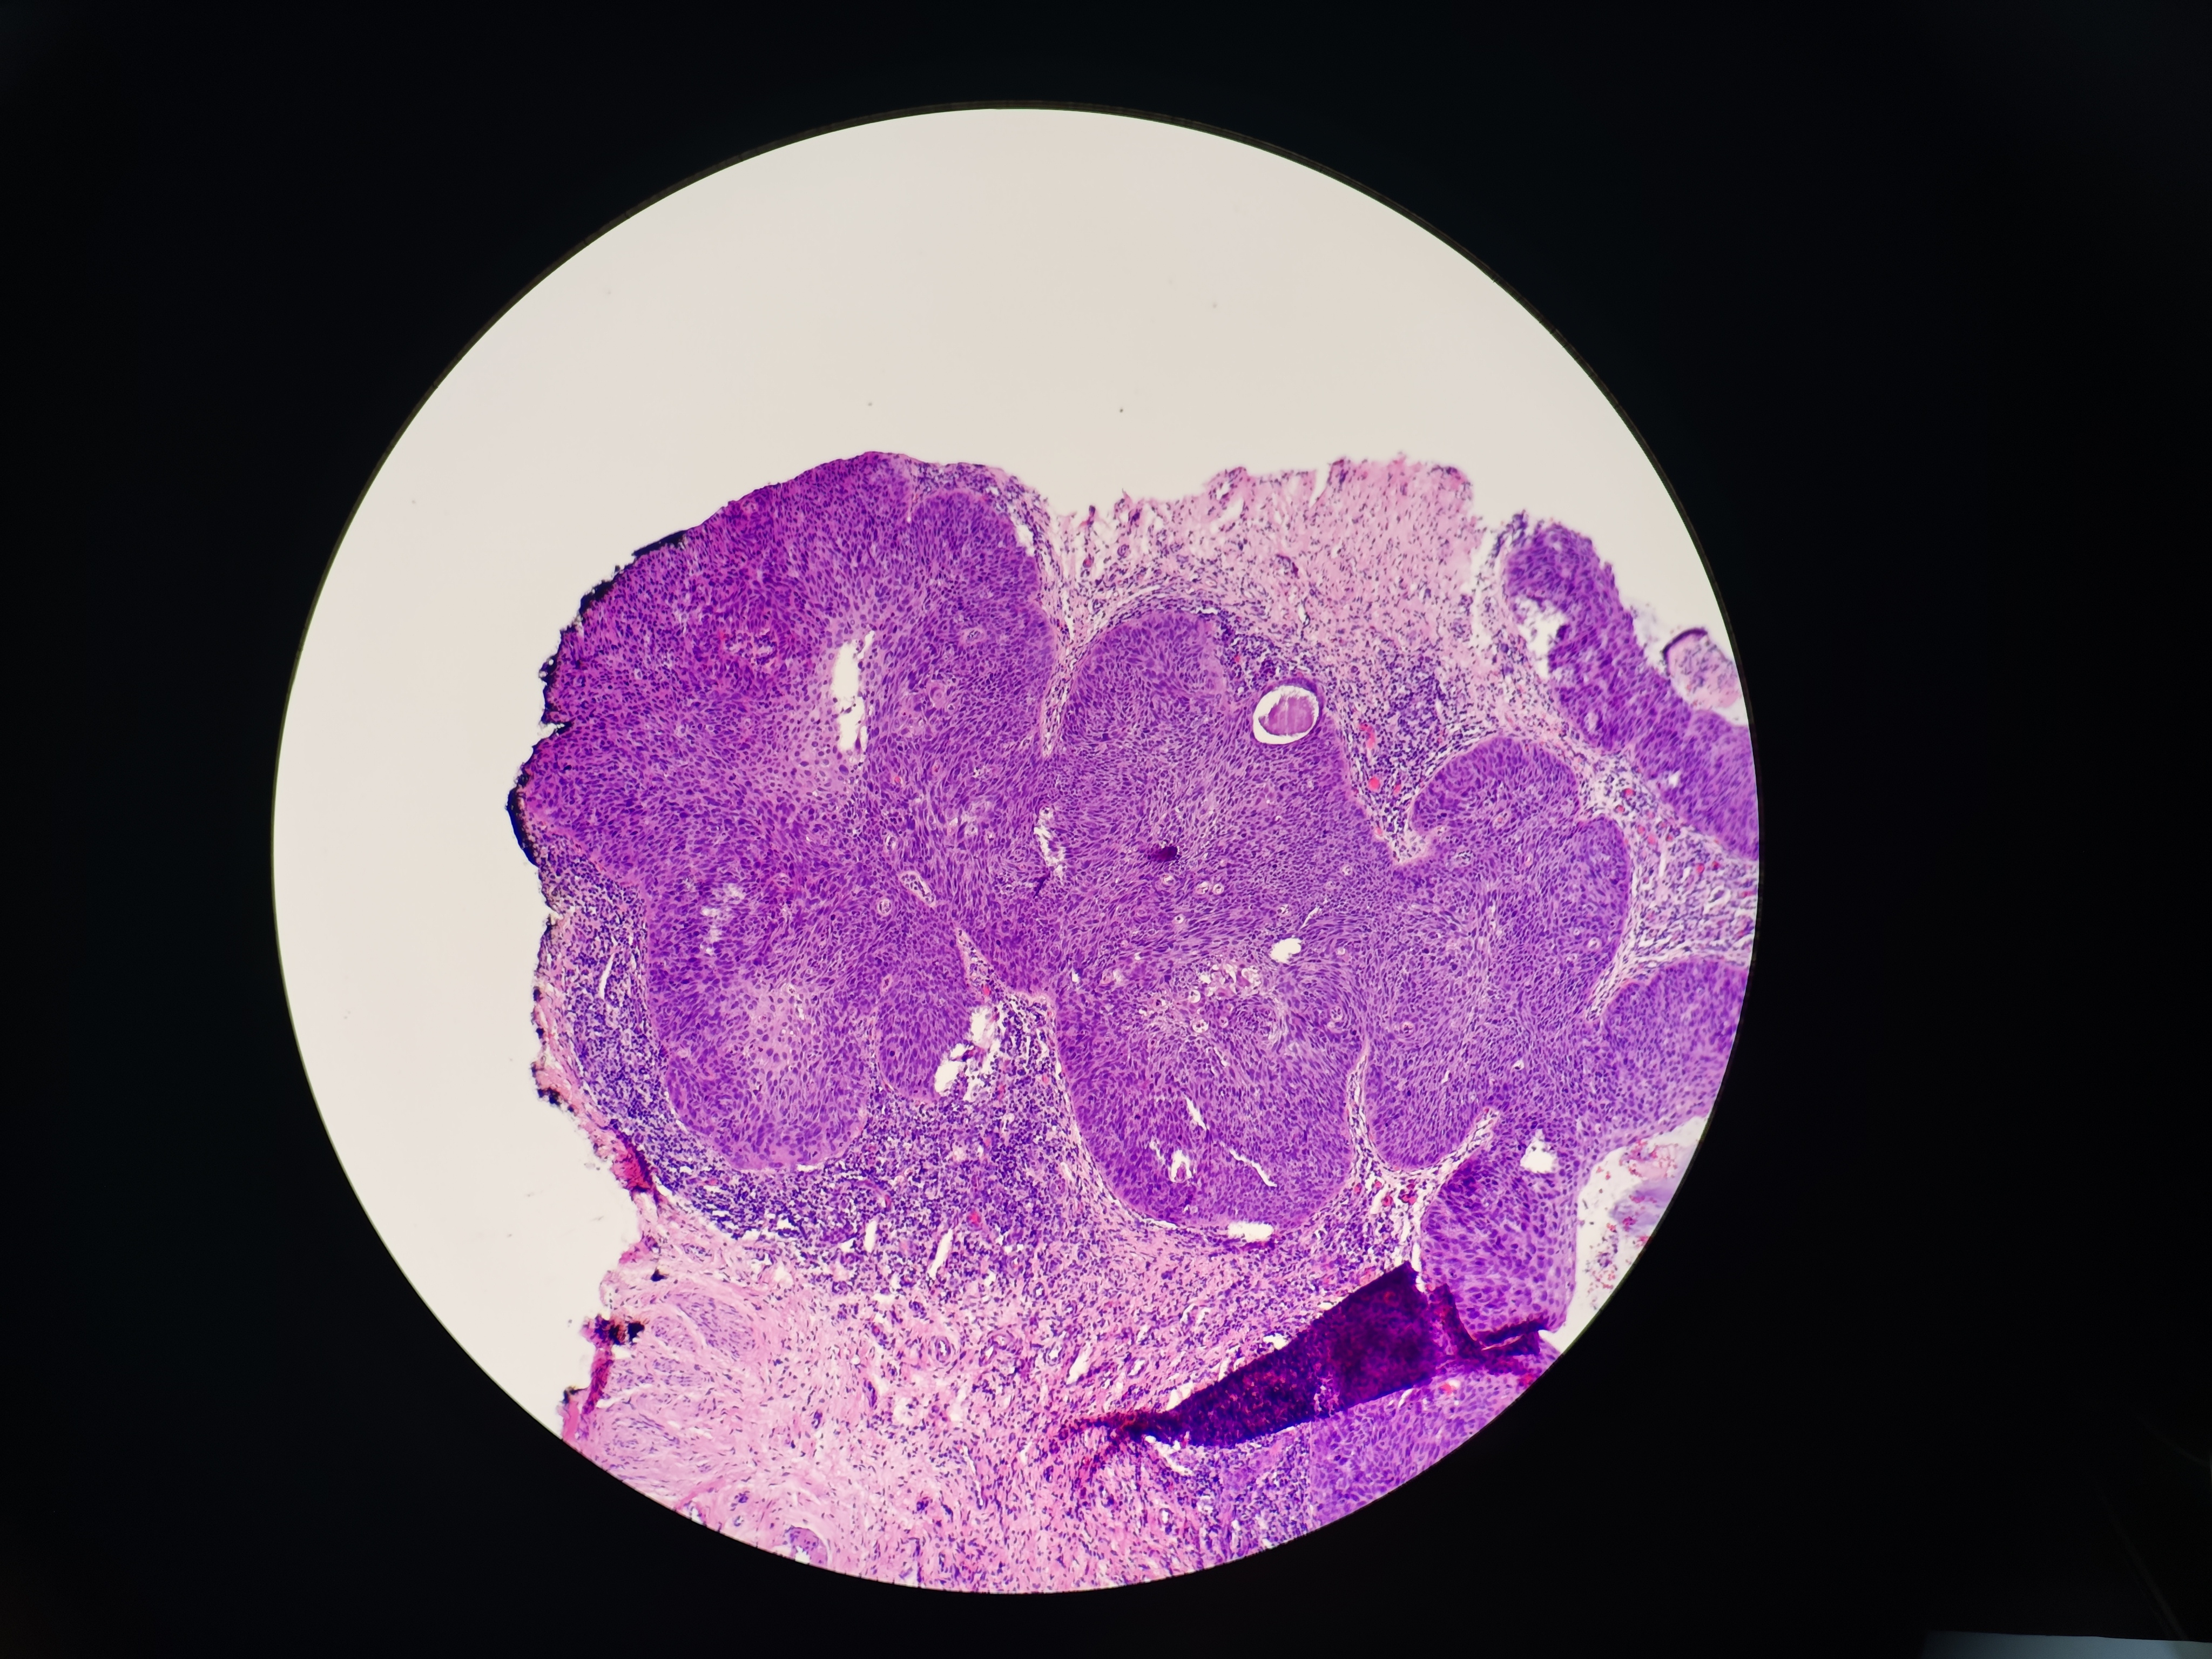

宫颈锥切

宫颈高级别病变

宫颈锥切标本

请教老师,这个到癌了吧? 图1~4是宫颈3点 图5-6是4点,这个是浸润还是累腺?

鳞癌